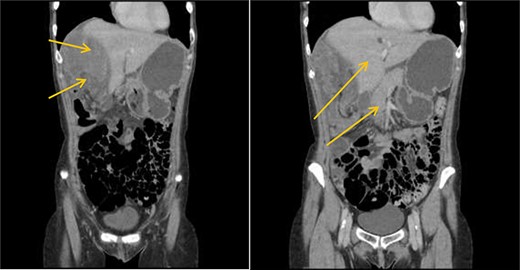

Patient initially diagnosed as biliary colic and surgical team had been contacted. Plain Abdominal radiograph showed dilated small bowels loops (Fig. 1). Chest radiograph revealed air under right hemi-diaphragm (Fig. 2). CT scan was done in emergency department and confirmed interposition of bowel between the diaphragm and the liver with a vascular/mesenteric pedicle swirl suggestive of malrotation or volvulus of the right colon. There was marked mural thickening and bold dilatation with high attenuation mucosa in keeping with closed loop obstruction and possible necrosis (Figs 3 and 4).

CT scan shows a vascular/mesenteric pedicle swirl suggestive of malrotation or volvulus with evidence of dilated closed loop obstruction.